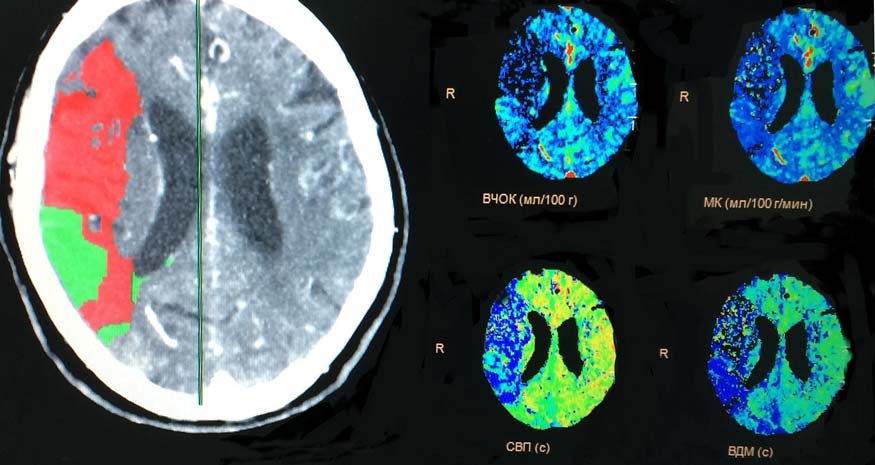

На полученных перфузионных картах рис. 1, 2) определяется крупная зона понижения показателей перфузии в правой височно-теменной области, что соответствует обеднению кровотока на данном уровне.

Рис. 1. Совмещение перфузионных карт с анатомическим срезом. Красным обозначено ядро инфаркта с внутричерепным объёмом крови 1,8 мл/100 г ткани (зона необратимых изменений). Зелёным цветом обозначена зона обратимой ишемии (пенумбра). Показатели перфузии: ВЧОК — внутричерепной объём крови; МК — мозговой кровоток; СВП — среднее время прохождения; ВДМ — время достижения максимума